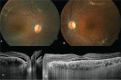

Figure 3

Figure 3. Fundus images from the left and right eyes taken 4 months after treatment. A) In the right eye, serous retinal detachment regressed to the level of the inferotemporal arcade, while a subretinal band is apparent at the level of the superotemporal arcade; B) In the left eye, subretinal fibrosis is apparent at the superior and inferior temporal arcades; C) Enhanced depth imaging-optic coherence tomography (EDI-OCT) in the right eye shows subretinal fluid and subfoveal choroid thickness of 537 µm in the section taken at the macula; D) EDI-OCT in the left eye revealed subretinal fluid in the macula, hyperreflective material in subretinal area, and subfoveal choroid thickness of 335 µm